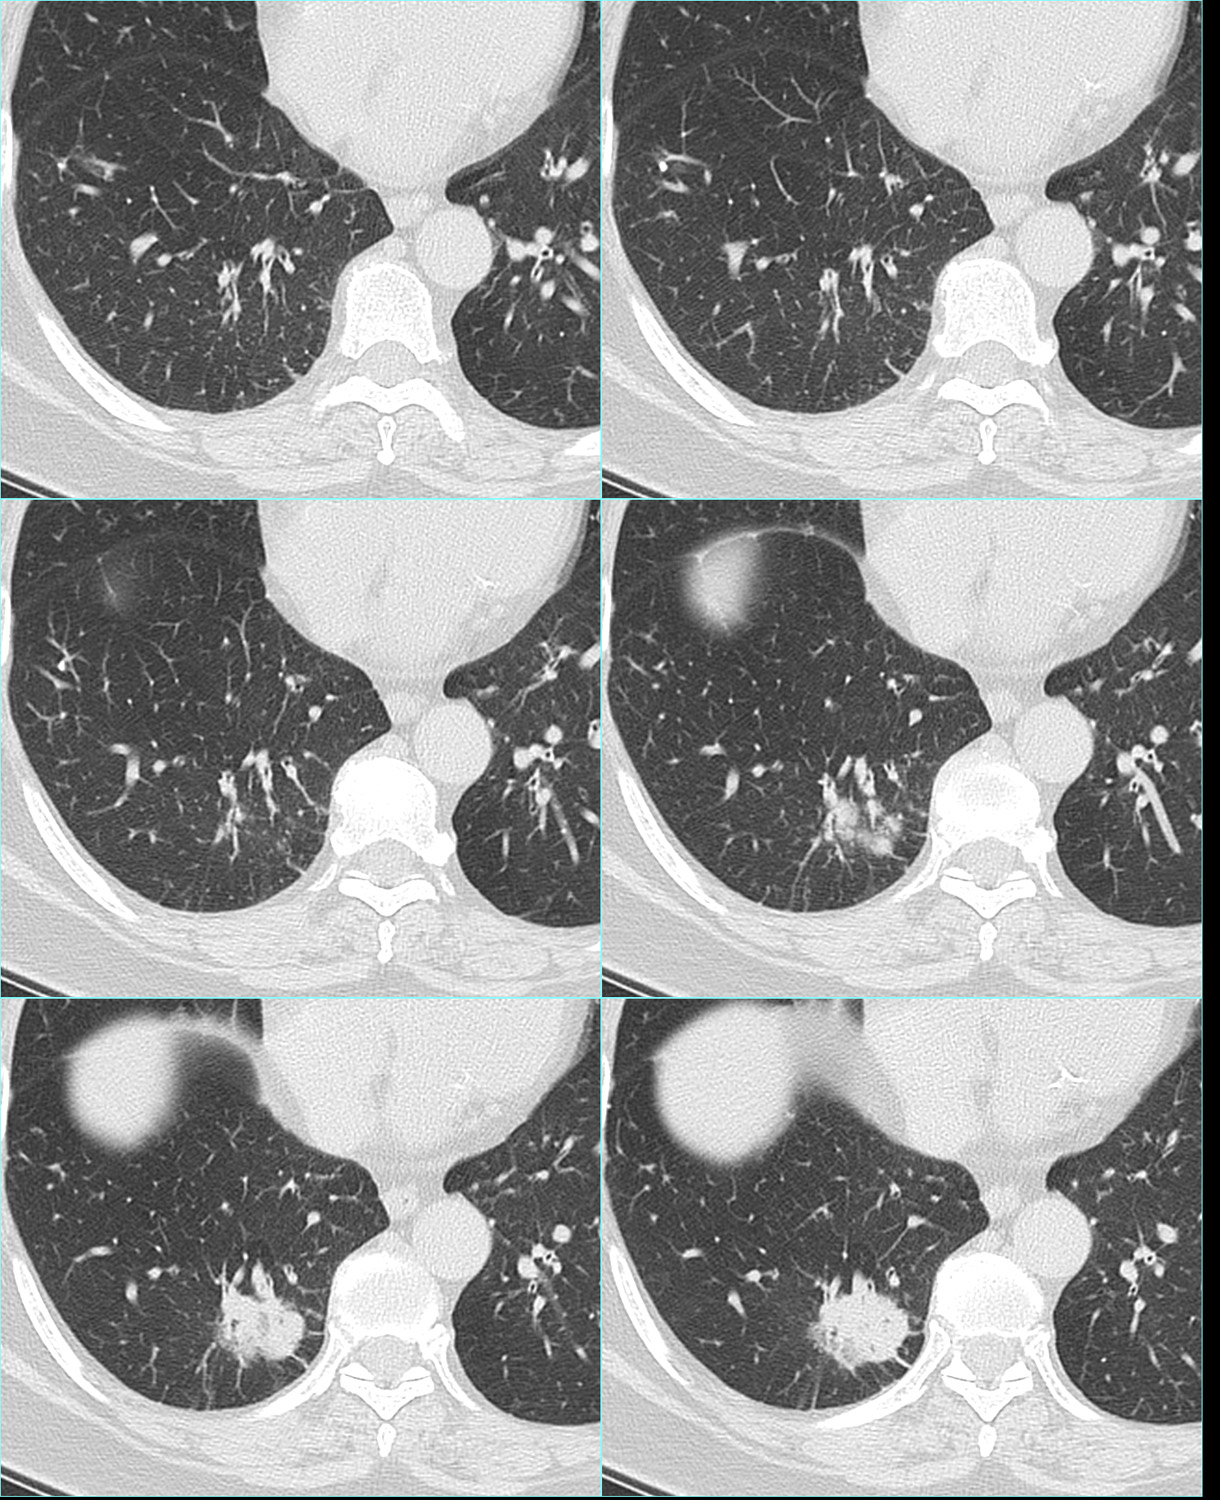

女69岁,咳嗽、咳痰、气喘、气短

患者于30年前无明显诱因出现咳嗽、咳痰、气喘、气短,呈阵发性,咳少许白粘痰,以活动后为著,无畏寒,发热,盗汗,胸痛等,曾多次在我院住院治疗,诊断为“慢性喘息型支气管炎”,给予抗炎,止咳,对症等治疗可好转 ...

右下肺见不规则结节影,边缘有毛刺及胸膜凹陷症。考虑:右下肺周围性肺癌。

右下肺可见外形不规则结节,边缘见短细毛刺及胸膜凹陷,内见透光区,主动脉旁见结节,考虑右下肺占位------周围型肺癌伴淋巴结转移可能性大。

右下肺可见外形不规则软组织密度肿块,边缘毛糙可见浅分叶,短细毛刺及胸膜凹陷,密度不均匀内见透光区,邻近胸膜增厚,综合考虑周围型肺癌。

右下肺后基底段周围型肺Ca,像是良性病变慢慢恶化而来的。

周围型肺癌可能性大,建议穿刺活检